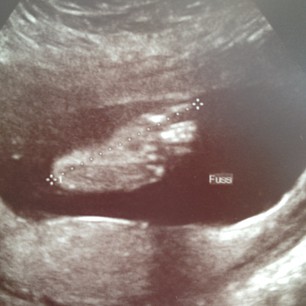

Ist das nicht ein süsser Käsemauke? :)Hey meine Lieben,

endlich komme ich mal wieder dazu hier ein wenig zu posten. Oben seht ihr ein paar Schnappschüsse aus der 21. - 26. SSW. Mittlerweile bin ich schon eine richtige kleine Kugel und ich liiiiiebe es ;)